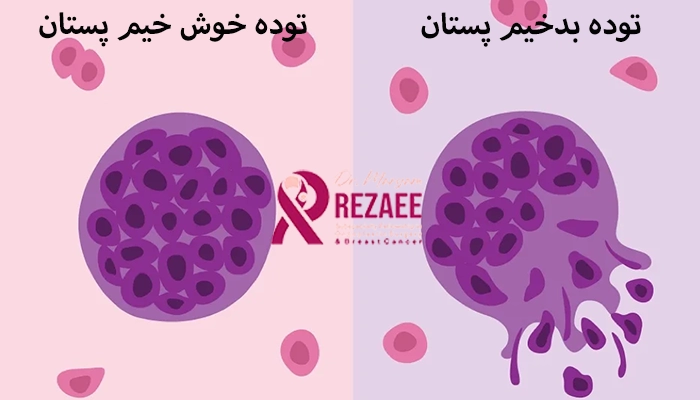

امکان دارد توده خوش خیم به توده بدخیم تبدیل شود؟

در بیشتر موارد، تودههای خوش خیم پستان به تودههای بدخیم تبدیل نمیشوند و خطری برای سلامت جدی ایجاد نمیکنند. این نوع تودهها ساختار مشخص و رفتار پایداری دارند و در طول زمان تغییر ماهیتی نمیدهند. بهعنوان مثال، فیبروآدنوم ها و کیست ها از جمله تودههای خوش خیمی هستند که به ندرت تبدیل به سرطان میشوند.

با این حال، برخی انواع خاصی از تودههای خوشخیم مانند هیپرپلازی آتیپیک با افزایش احتمال ابتلا به سرطان پستان در آینده همراه است. این نوع ضایعات بدخیم نیستند که مستقیماً به سرطان تبدیل شوند، بلکه زمینه ای را فراهم میکنند که احتمال بروز سرطان را کمی بالا میبرد. به همین دلیل، پیگیری منظم، ماموگرافی های دورهای و مشورت با پزشک برای این دسته از بیماران بسیار مهم است.

| ویژگی | توده خوش خیم پستان | توده بدخیم پستان |

|---|---|---|

| رشد | آهسته | سریع |

| مرز توده | مشخص و منظم | نامنظم |

| درد | معمولاً بدون درد | گاهی دردناک باشد |

| حرکت پذیری | متحرک | ثابت و چسبیده به بافت |

| خطر متاستاز | ندارد | دارد |

توده خوش خیم معمولا نرم، متحرک و با مرز مشخص است، در حالی که توده بدخیم سفت، ثابت و با مرز نامنظم دیده میشود و نیاز به بررسی فوری دارد.